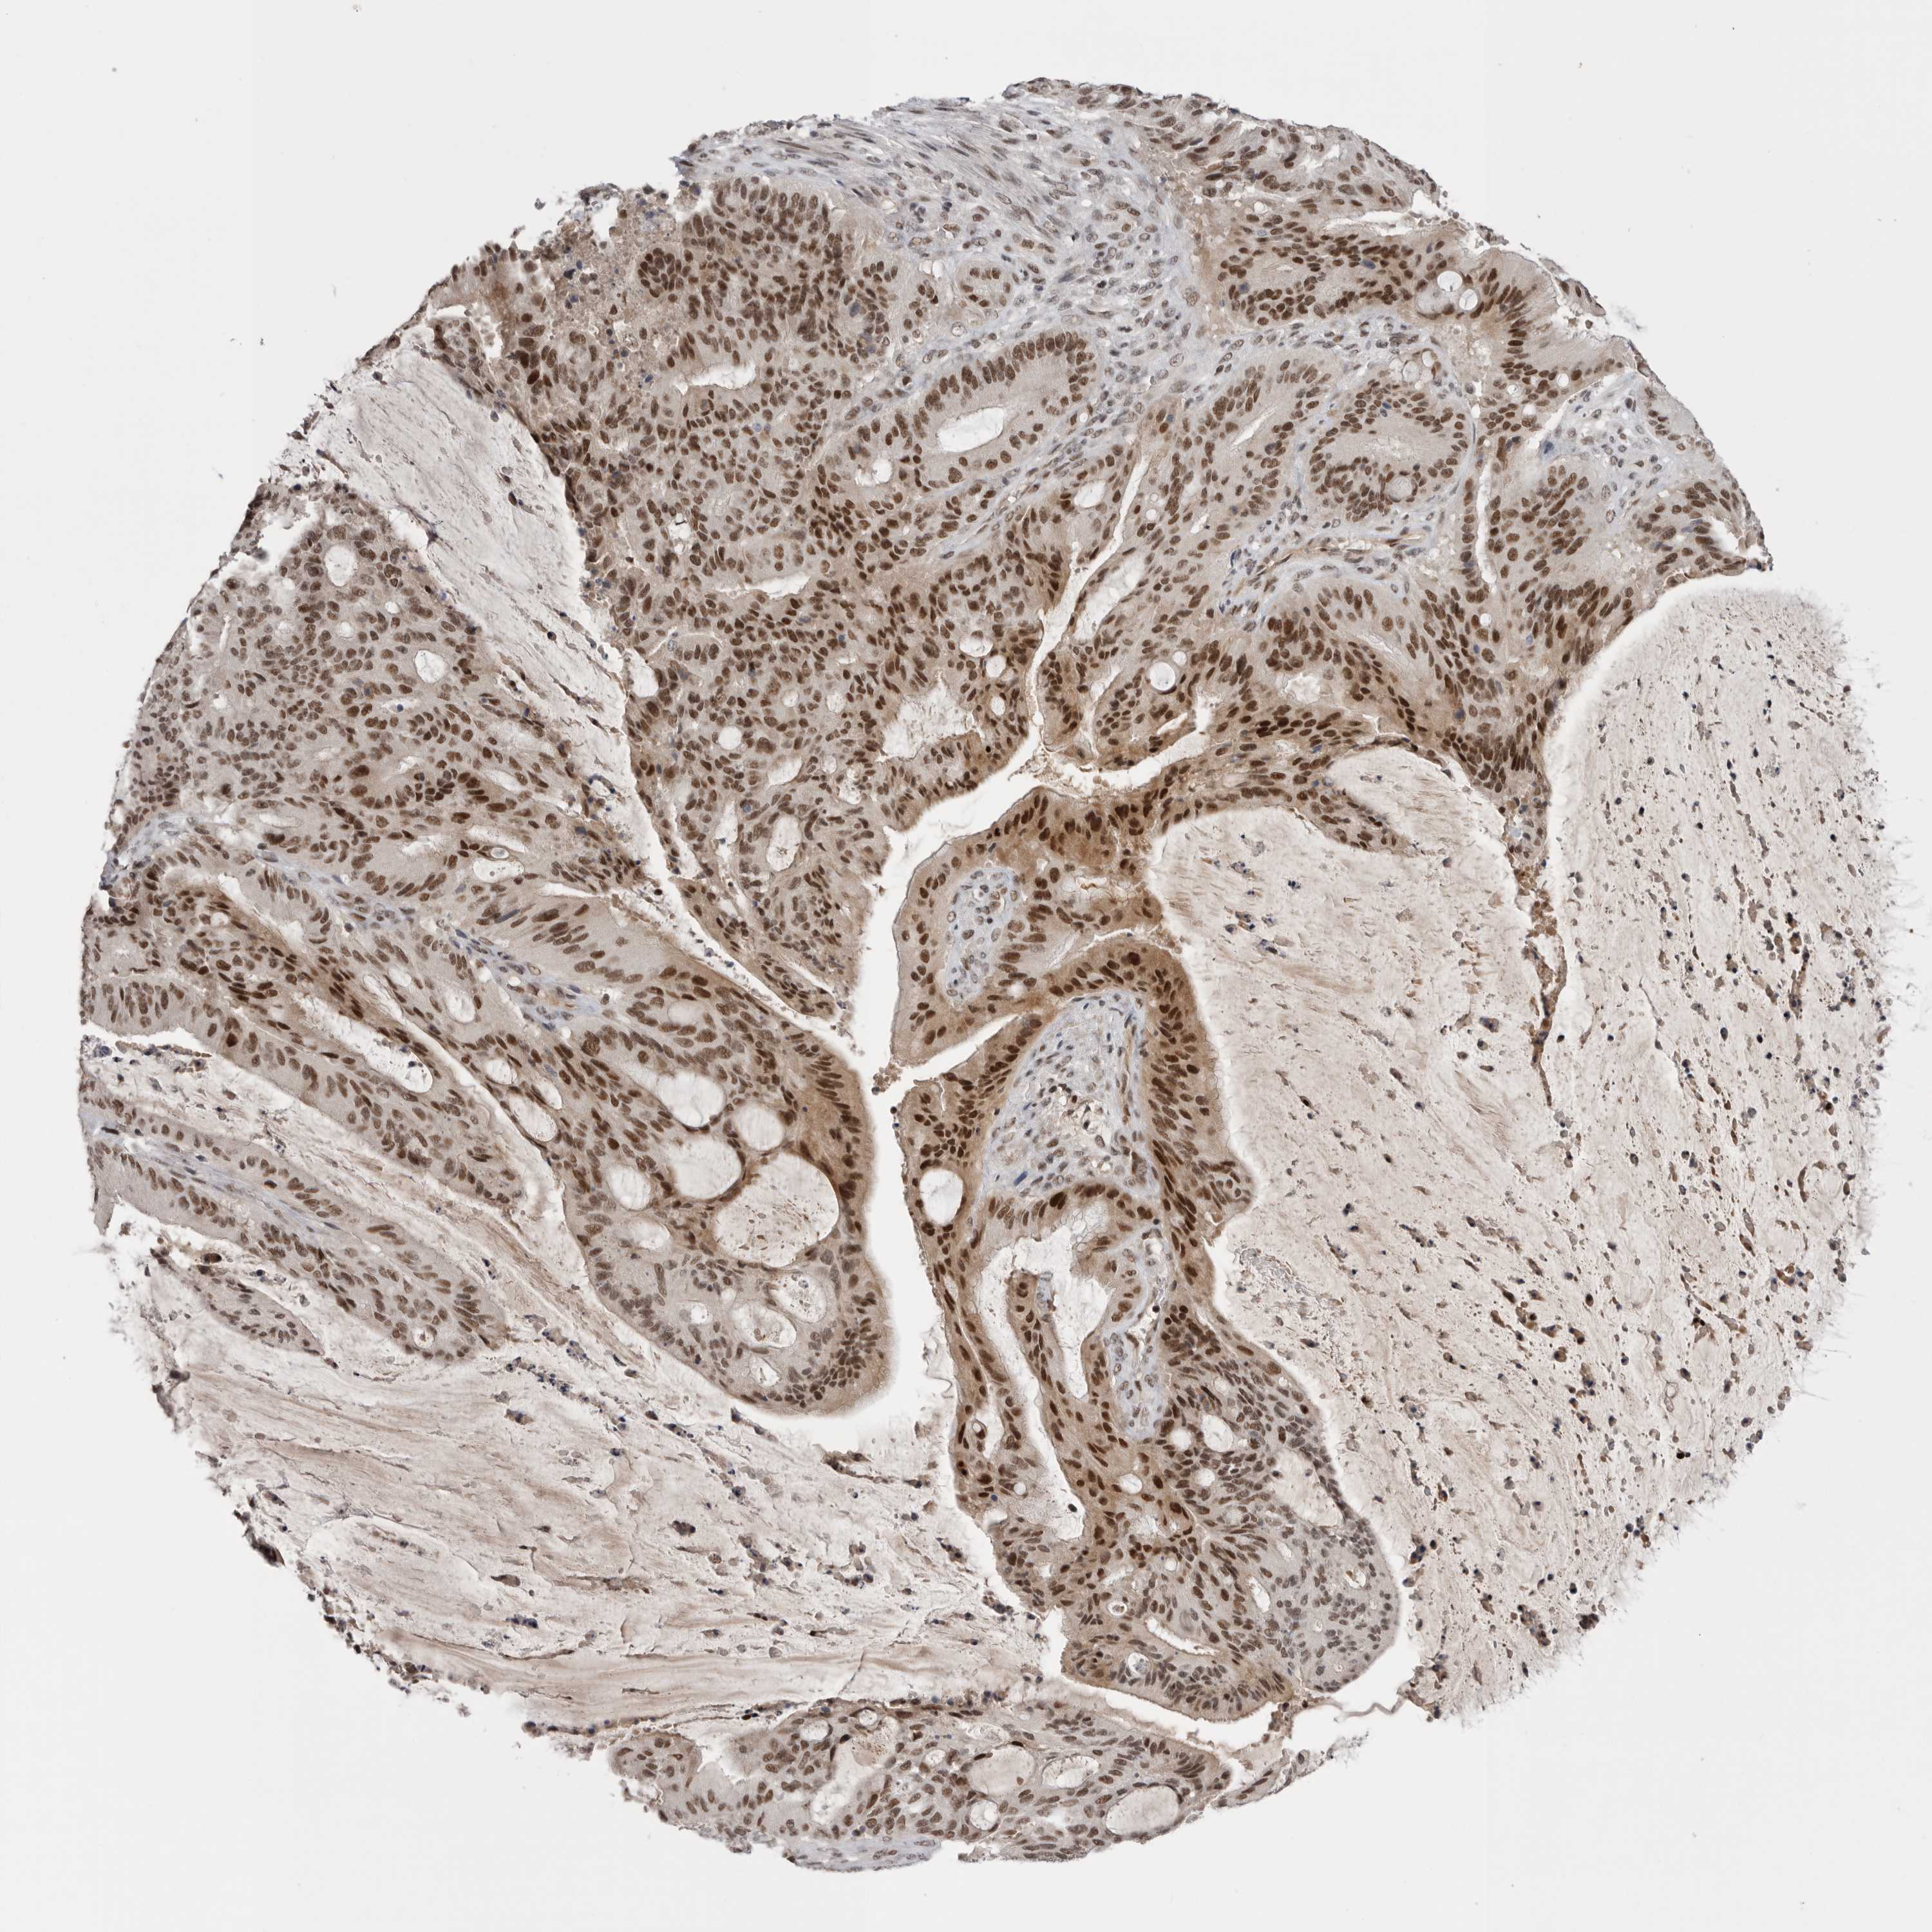

LIVER CANCER - Protein expressioni

A mouse-over function shows sample information and annotation data. Click on an image to view it in a full screen mode. Samples can be filtered based on level of antibody staining by selecting one or several of the following categories: high, medium, low and not detected. The assay and annotation is described here.

Note that samples used for immunohistochemistry by the Human Protein Atlas do not correspond to samples in the TCGA dataset.

Antibody stainingi

Antibody staining in the annotated cell types in the current human tissue is reported as not detected, low, medium, or high, based on conventional immunohistochemistry profiling in selected tissues. This score is based on the combination of the staining intensity and fraction of stained cells.

Each image is clickable and will lead to virtual microscopy that enables deeper exploration of all samples and also displays staining intensity scores, fraction scores and subcellular localization as well as patient and tissue information for each sample.

Antibody CAB025600

Antibody CAB026380

Antibody CAB079773

Staining

High

Medium

Low

Not detected

Intensity

Strong

Moderate

Weak

Negative

Quantity

>75%

75%-25%

<25%

None

Location

Nuclear

Cytoplasmic/membranous

Cytoplasmic/membranous,nuclear

Cholangiocarcinoma

Carcinoma, Hepatocellular, NOS